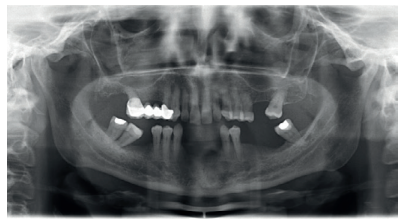

Aft er 4 years, the second and third quadrant molars began to have excessive mobility and serious periodontal problems, so it was decided to remove them and regenerate the alveoli with PRGF-Endoret. Once the area was regenerated (a month and a half later), a conebeam was performed to evaluate the residual bone volume. It can be seen how there was an uneven bone crest with areas of 3.3 mm in height up to a maximum of 7 mm (Figures 9 and 10). On this occasion, due to the protocol change described above, we opted for the direct insertion of extra-short implants, since the surgical protocols to address this type of situation in 2011 varied substantially, with these implants being a first-line tool for the treatment of this type of atrophy (Figure 11). Two extra-short implants were selected (5.5 mm diameter x 6.5 mm length for tooth 26, and 6 mm diameter x 5.5 mm length for tooth 27).